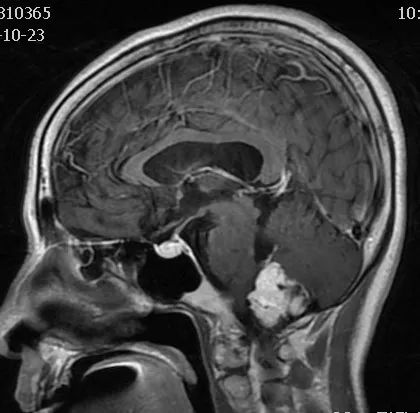

6-T1ensag

FLAIR图及T1矢状位增强:白色箭头所示小脑延髓池内可见实性占位病变,形态不规则,呈分叶状,病变边界清晰,边缘见血管流空信号影如蓝色箭头所示。

影像描述:小脑延髓池内见不规则异常信号影,呈等及稍长T1长T2信号,内部信号不均,边缘见稍粗大流空信号血管影,FLAIR病灶中心少许片状低信号,增强呈明显强化,DWI不均低信号,ADC不均高信号。小脑半球、延髓、第四脑室受压变形。临近延髓受压变窄,呈长T1长T2信号。

影像诊断:后颅窝实性占位病变,斟酌实性血管母细胞瘤。